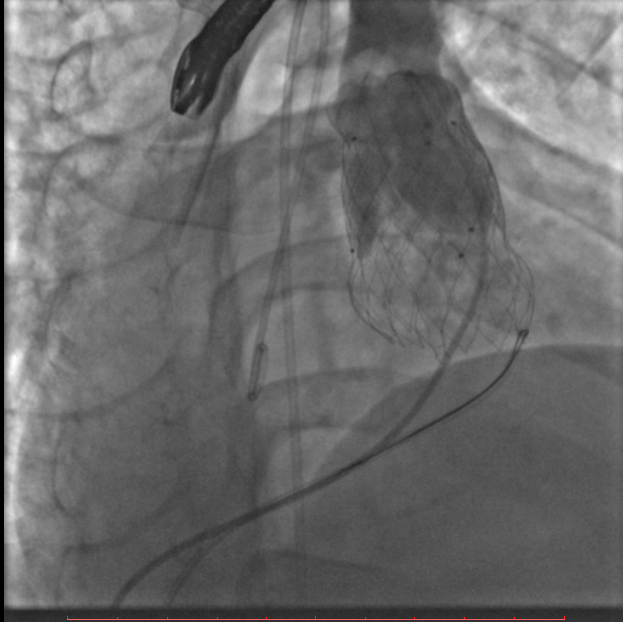

葛院士团队评估后认为,患者右肺动脉因阻挡存在狭窄,且右肺动脉与主肺动脉压差较大,具有临床意义,存在解决的必要。先后尝试Snare圈套瓣架下缘下拉法、双导管圈套瓣架上缘下拉法,但效果不理想,复测右肺动脉与主肺动脉压差仍较大,选择性右肺动脉造影仍存在右肺动脉狭窄。但考虑到患者利益,在安全操作的基础上,团队仍未放弃。拟通过将球囊送至右肺动脉开口处扩张,达到下压瓣膜支架、解除右肺动脉狭窄的效果,考虑到该操作的难点在于球囊无法顺畅到达肺瓣上目标位置,决定采用简略版PASS技术,即通过辅路送Snare至右肺动脉开口,并利用该Snare圈套住主路的Lunder quist导丝,换言之,即通过Lunder quist导丝两头发力将三尖瓣-右室流出道-右肺动脉这一扭曲的途径直线化且增强Lunder quist导丝支撑力,同时,由于Lunder quist导丝在右肺动脉处有附着力,可以避免瓣膜下移过多,如此球囊顺利通过瓣膜支架网孔进入右肺动脉,在DSA指引下逐步扩张球囊,成功使人工瓣膜支架向右心室侧移位。复查造影提示右肺动脉开口未见明显阻挡(图五),复测主肺动脉、左肺动脉、右肺动脉压力分别为32/9/19mmHg、32/7/18mmHg、29/7/17mmHg。复查肺动脉主干造影,显示人工瓣膜启闭良好,轻微瓣膜反流。最终手术疗效显著、取得令人满意的结果。

图五:通过PASS技术将球囊送至右肺动脉开口并扩张球囊、完成肺动脉瓣膜支架向心室侧移位,复查造影右肺动脉未见明显阻挡